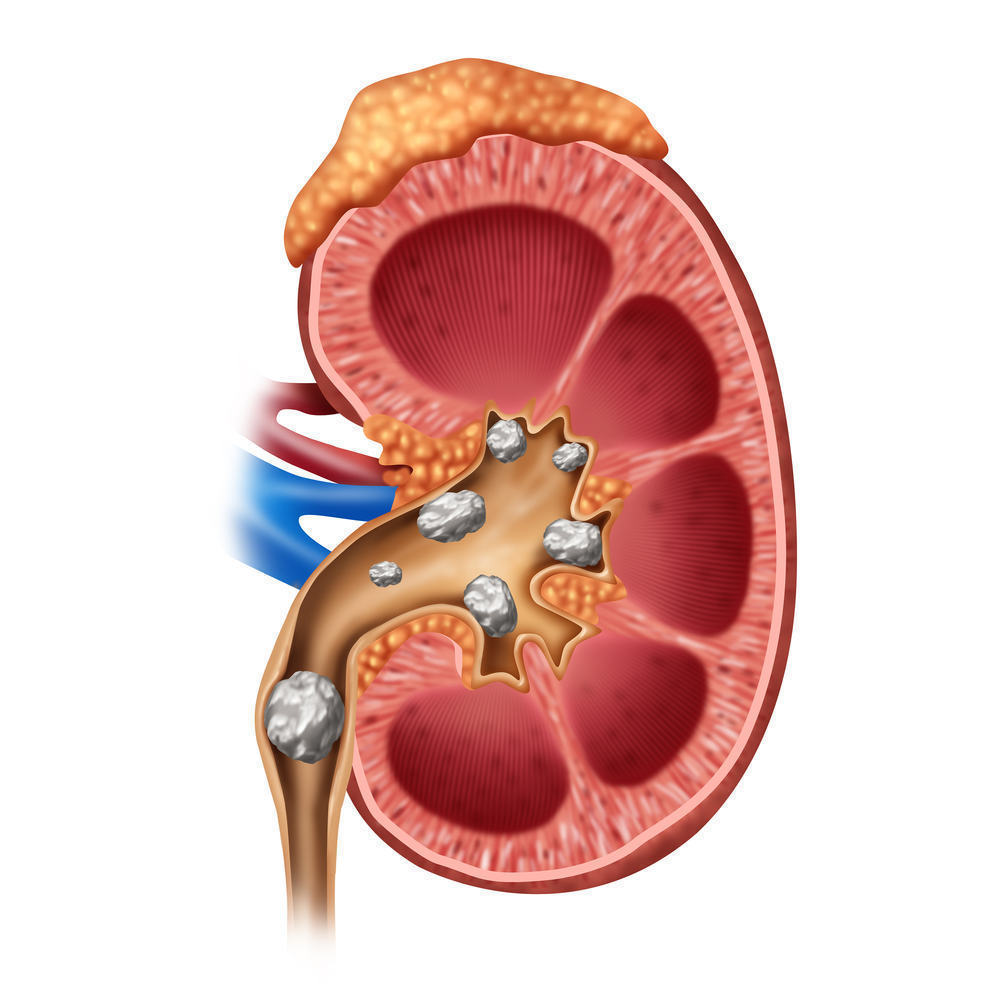

Batu Ginjal dan Dampaknya: Kenali Sebelum Terlambat

Batu ginjal adalah kondisi medis yang terjadi ketika mineral dan garam dalam urin mengkristal dan membentuk massa keras di dalam ginjal. Proses ini biasanya dipicu oleh konsentrasi zat tertentu yang terlalu tinggi dalam urin, seperti kalsium, oksalat, atau asam urat. Ginjal yang berfungsi menyaring limbah dari darah seharusnya menghasilkan urin yang seimbang, namun ketika keseimbangan ini terganggu, kristal dapat terbentuk dan berkembang menjadi batu. Ukuran batu ginjal bervariasi, mulai dari sekecil butiran pasir hingga sebesar bola kecil, dan keberadaannya dapat menyebabkan rasa nyeri yang sangat hebat ketika bergerak melalui saluran kemih.

Penyebab batu ginjal sangat beragam dan sering kali dipengaruhi oleh gaya hidup serta faktor kesehatan tertentu. Kurangnya asupan cairan merupakan salah satu faktor utama, karena urin yang terlalu pekat memudahkan pembentukan kristal. Pola makan yang tinggi garam, protein hewani, dan oksalat juga dapat meningkatkan risiko. Selain itu, kondisi medis seperti obesitas, gangguan metabolisme, infeksi saluran kemih, serta riwayat keluarga dengan batu ginjal turut berperan dalam meningkatkan kemungkinan seseorang mengalami kondisi ini. Beberapa jenis batu ginjal yang umum meliputi batu kalsium, batu asam urat, batu struvit, dan batu sistin, masing-masing dengan karakteristik dan penyebab yang berbeda.

Penanganan batu ginjal tergantung pada ukuran, jenis, dan tingkat keparahannya. Batu kecil biasanya dapat keluar dengan sendirinya melalui urin dengan bantuan konsumsi air yang cukup dan obat pereda nyeri. Namun, untuk batu yang lebih besar atau menyebabkan komplikasi, diperlukan tindakan medis seperti terapi gelombang kejut (ESWL) untuk memecah batu, ureteroskopi untuk mengangkat batu melalui saluran kemih, atau operasi dalam kasus yang lebih serius. Selain itu, dokter juga dapat meresepkan obat-obatan tertentu untuk membantu melarutkan batu atau mencegah pembentukan kembali, tergantung pada jenis batu yang dialami pasien.

Pencegahan batu ginjal sangat penting untuk menghindari kekambuhan, karena kondisi ini cenderung berulang jika tidak ditangani dengan baik. Salah satu langkah paling efektif adalah menjaga asupan cairan dengan minum air putih minimal dua hingga tiga liter per hari agar urin tetap encer. Mengurangi konsumsi garam, membatasi protein hewani, serta menghindari makanan tinggi oksalat seperti bayam dan cokelat juga dapat membantu. Selain itu, menjaga berat badan ideal dan rutin melakukan pemeriksaan kesehatan sangat dianjurkan, terutama bagi individu yang memiliki risiko tinggi. Dengan perubahan gaya hidup yang tepat dan kesadaran akan pentingnya kesehatan ginjal, risiko batu ginjal dapat diminimalkan secara signifikan.